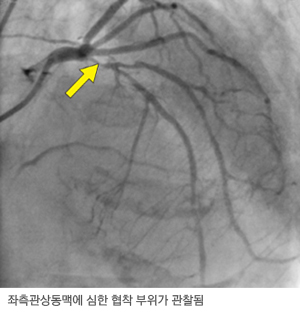

관상동맥조영술은 조영제가 심장동맥으로 퍼져가는 과정이 동영상으로 촬영된다. 관상동맥은 크게 3개의 주요 혈관이 있고, 이 중 2개는 하나의 시작 부위로부터 갈라지고, 다른 하나는 별도의 시작 부위로부터 나온다. 또한 각 혈관으로부터 여러 혈관 분지들이 갈라져 나오고 이런 주요 혈관들의 내경은 2~4mm 정도이다. 그러므로 적어도 2개의 다른 관을 이용해서 각각의 입구를 찾아야 하고 한번 입구를 찾으면 그 상태에서 여러 각도에서 촬영을 하여 혈관이 좁아진 병변이 있을 경우에는 병변의 정확한 위치와 협착의 정도를 평가하게 된다.

관상동맥 조영술 영상